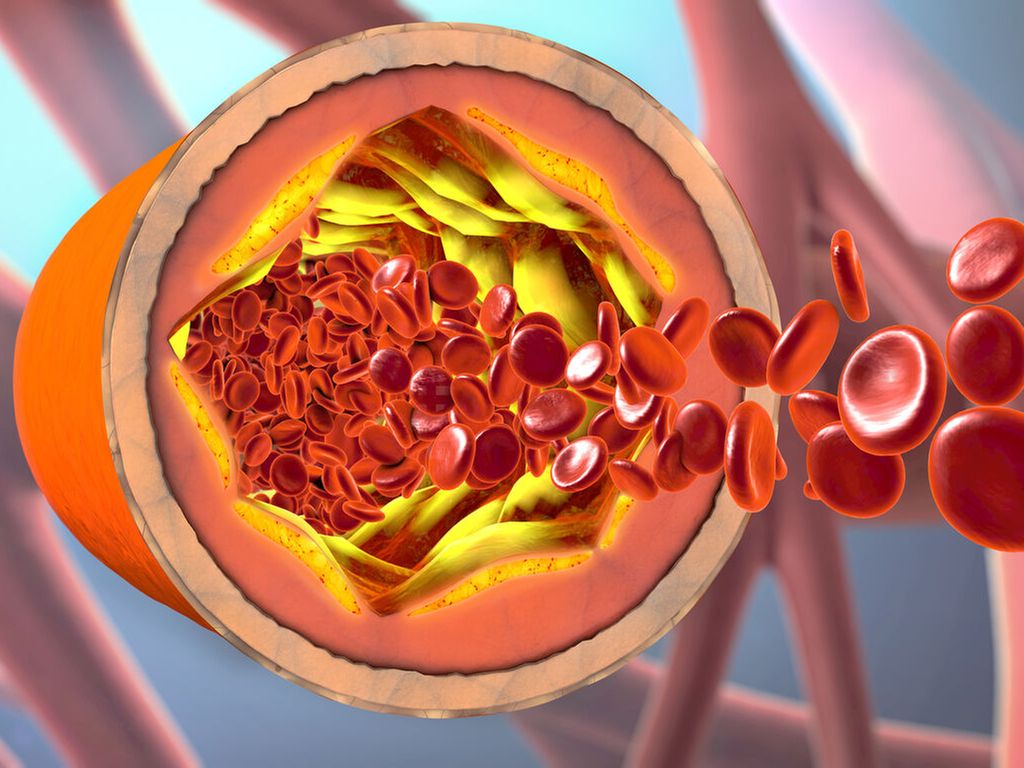

Hyperlipidämie und kardiovaskuläres Risiko bei Typ-2-Diabetes